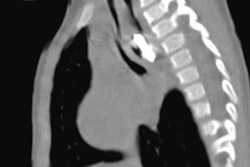

Esophagram shows a leak of contrast into the retropharyngeal soft tissues.In cases of foreign body ingestion, it's important to consider that there may be parts x-ray can't identify, the researchers concluded.